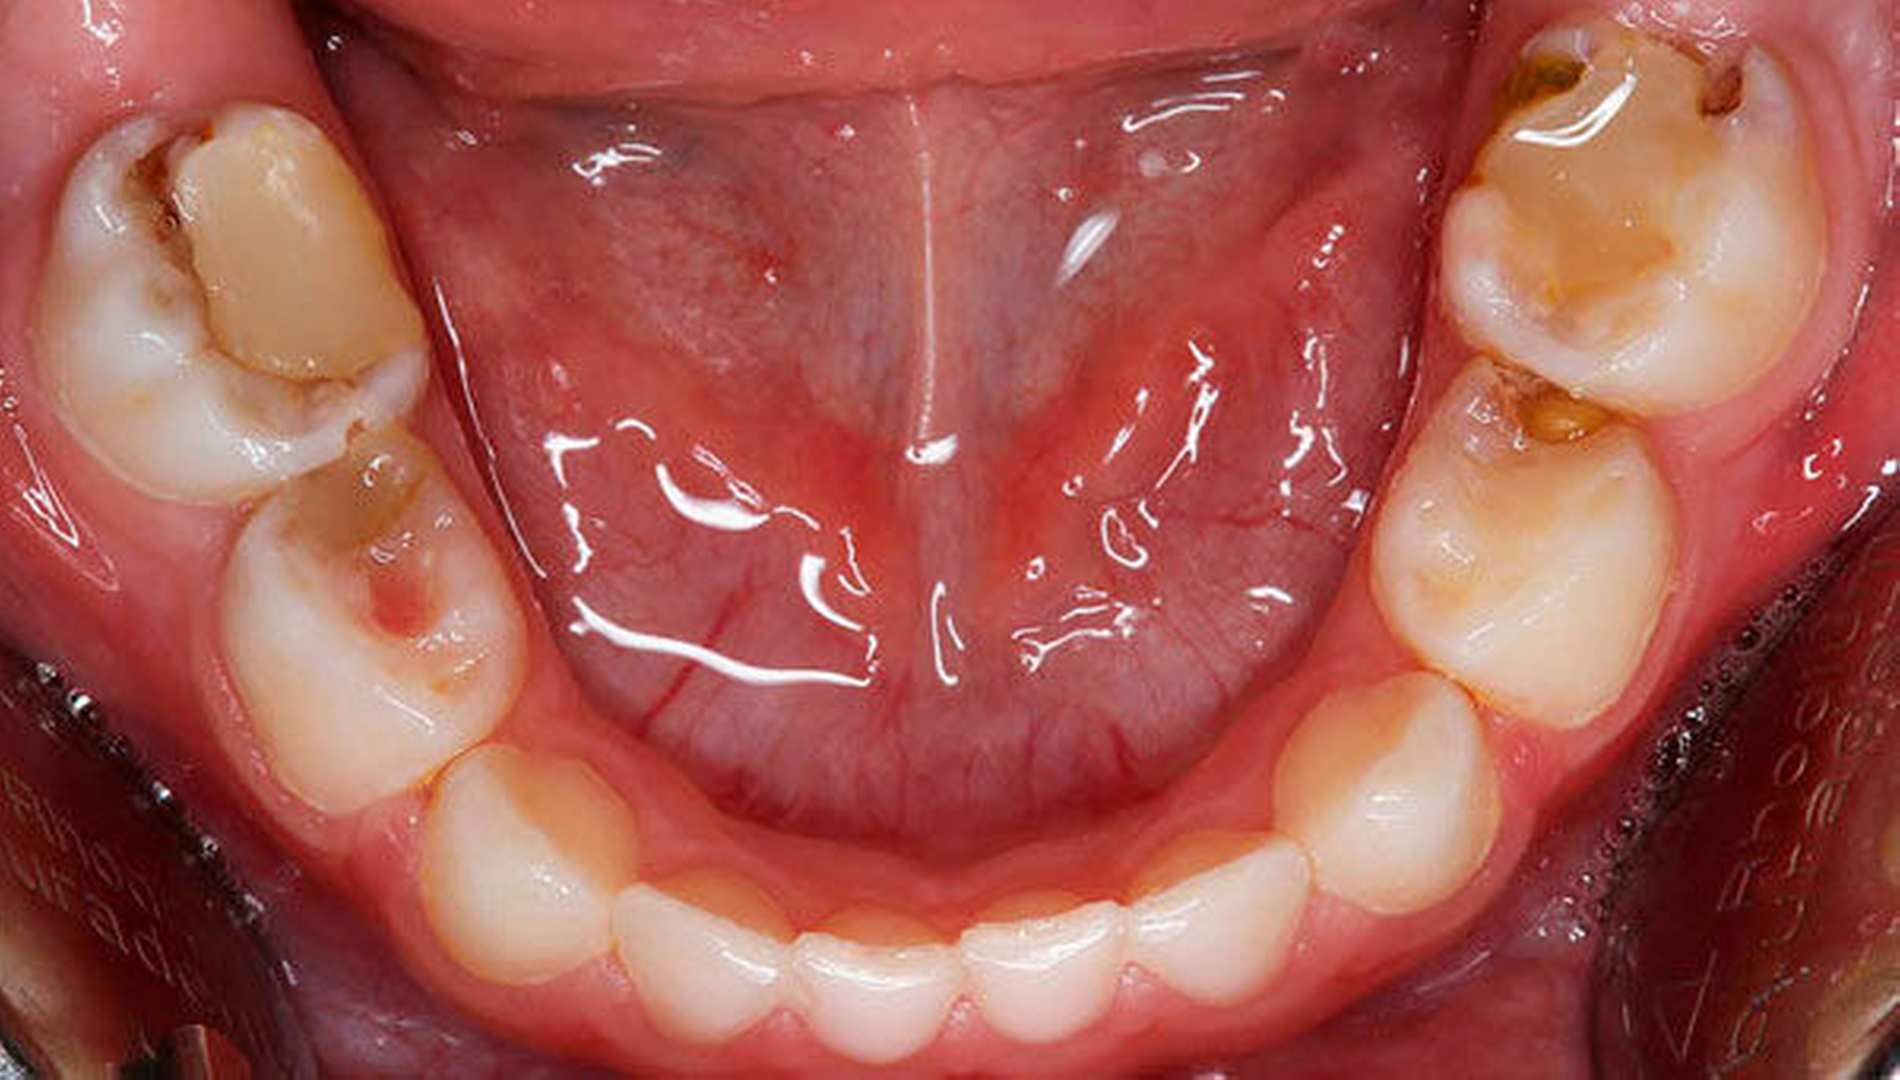

Somit ist die konventionelle Füllungstherapie am Milchmolar, vorzugsweise mit lichthärtendem Glasionomerzement oder Komposit, nur bei kleinen maximal zweiflächigen Kariesdefekten mit ausreichender Dentinschichtstärke zur Pulpa sinnvoll. Da der Milchzahnschmelz auch eine geringere Mineralisation mit aprismatischen Bereichen und größerem Porenvolumen aufweist, ist er schlechter anätzbar [Van Waes und Stöckli, 2001]. Zudem wird durch die reduziertere Schmelzdicke der adhäsive Verbund zwischen Zahnhartsubstanz und Komposit verringert. Bei der Füllungsgestaltung ist ein kinderfreundliches Matrizensystem, beispielsweise die T-Band-Matrize (Pulpdent, USA) ohne Matrizenhalter, empfehlenswert. Im Zuge der Quadrantensanierung lassen sich zwei angrenzende approximale Kavitäten bei guter Verkeilung problemlos füllen, ohne auf einen straffen Kontaktpunkt verzichten zu müssen (Abbildung 5). Dieses Vorgehen spart Zeit und findet bei den Kindern gute Akzeptanz. Die Anschaffung des erforderlichen Instrumentariums lohnt sich auch als Anschaffung für die allgemeinzahnärztliche Praxis.

Da die Füllungstherapie im Milchgebiss sehr schnell an ihre Grenzen stößt und bei nicht adäquaten Restaurationsdefekten das Risiko eines Füllungsverlusts oder einer Sekundärkaries (Abbildung 10) besteht [Van Waes, 1993], stellt die konfektionierte Kinderkrone in vielen Fällen die einzige Möglichkeit zum Zahnerhalt dar.